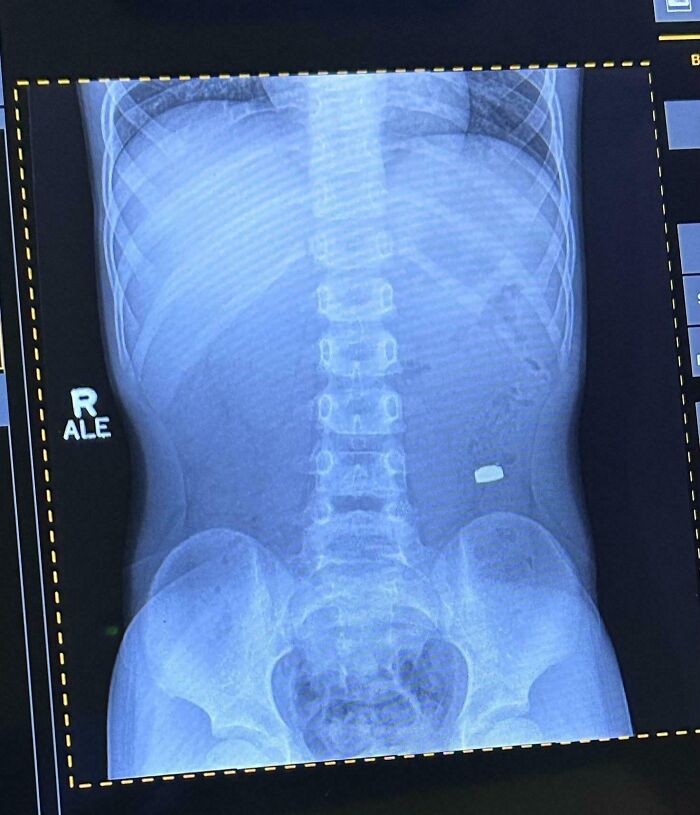

Mi hijo se tragó un centavo mientras le mostraba a su hermano pequeño cómo se había tragado accidentalmente una clave SIM el día anterior.